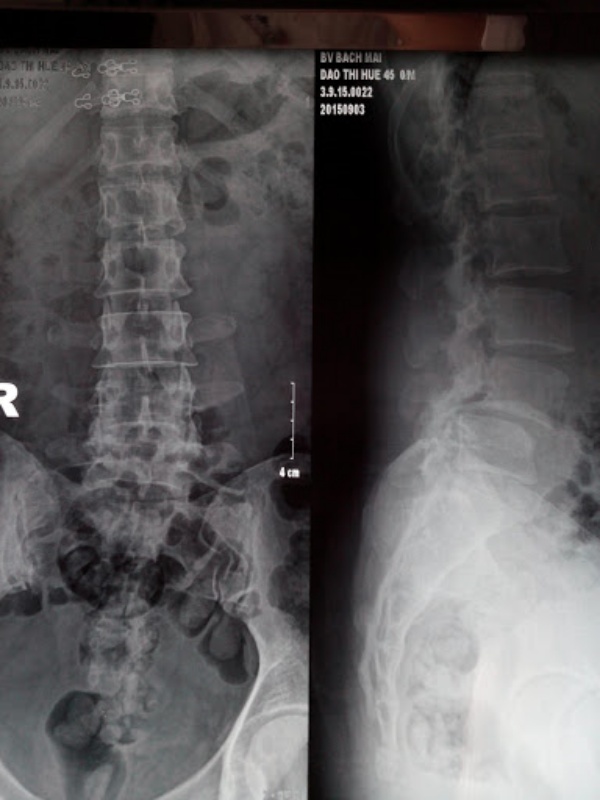

Cận lâm sàng: Đánh giá đặc điểm TĐS trên X-quang thẳng, nghiêng, chếch 3/4 trái- phải, nghiêng cúi – ưỡn tối đa. Đánh giá chiều cao đĩa đệm trước mổ, phân loại nguyên nhân TĐS, phân độ TĐS theo phân loại của Meyerding. MRI đánh giá hẹp ống sống hay lỗ liên hợp.

Đặc điểm chẩn đoán hình ảnh

Có 2 BN (6,7%) bị TĐS do khuyết eo, 93,3% do thoái hóa. Trượt độ I chiếm 86,7%, còn lại độ II và độ III. Chiều cao đĩa đệm trước mổ trung bình 8,0 ± 2,5 mm (3 – 11 mm). 27 BN (90%) có hình ảnh hẹp ống sống, 03 BN (10%) có hình ảnh hẹp lỗ liên hợp trên phim MRI.

Xquang: Trên phim Xquang cột sống thắt lưng có 93,3% BN bị TĐS do thoái hóa, chỉ có 2 BN (6,7%) bị TĐS do khuyết eo gặp ở bệnh nhân trẻ tuổi. Đánh giá mức độ TĐS theo Meyerding, trượt độ I chiếm 86,7%, còn lại độ II và độ III. Kết quả này tương đồng với một số nghiên cứu khác như: Phan Trọng Hậu trượt độ I là 51,4%, độ II là 41,4%, độ III là 7,2%; Phan Minh Đức có kết quả trượt độ I là 69%, độ II là 30%, độ III là 1%.

Chiều cao đĩa đệm đốt sống trượt trước mổ trung bình 8,0 ± 2,5 mm (3 – 11 mm). Nghiên cứu của H. N. Herkowitz và cộng sự, chiều cao đĩa đệm trung bình là 6.8 mm. Giải thích điều này chúng tôi cho rằng nhóm BN của chúng tôi thấp tuổi hơn, tỷ lệ thoái hóa đĩa đệm gặp ít hơn.